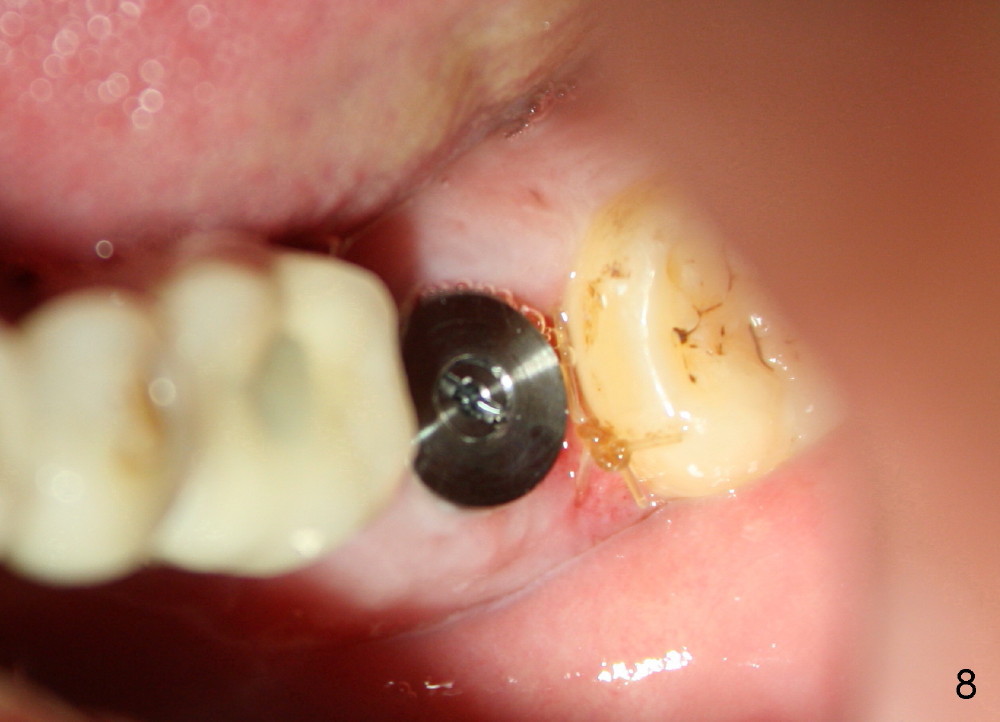

The septum of the socket is thin (Fig.3*), and easily removed, leaving a large socket. Osteotomy is initiated with 2 mm pilot drill in the middle of the socket, slightly mesiolingual, since the buccal and distal bone is low and defective. Reamers (2.5 to 4 mm in diameter) are sequentially used to enlarge osteotomy and harvest autogenous bone (Fig.4 (3 mm reamer in place). When 5 mm tap is placed, there is no stability. Six mm tap gains some stability, but the socket is not closed. Seven mm tap achieves strong stability and is closing the socket (Fig.5). Ultimately a 7x14 mm implant is placed with insertion torque more than 60 Ncm (Fig.6). The implant almost obliterates the socket (Fig.7). The harvested autogenous bone is placed in the buccal and distal aspects of the socket before Chromic gut suture (4-0) is placed distally. Fig.8,9 show the healing socket 6 days and 1.5 months postop, respectively. Osteointegration appears to occur in 2.5 months (Fig.10, compare to Fig.6). Bone level remains the same 1 year post cementation (Fig.11).